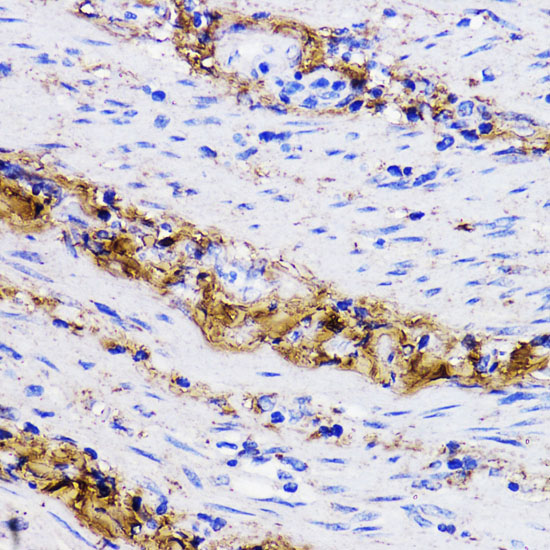

Immunohistochemistry of paraffin-embedded human placenta using COL1A1 at dilution of 1:200 (40x lens).

Immunohistochemistry of paraffin-embedded rat ovary using COL1A1 at dilution of 1:200 (40x lens).

Immunohistochemistry of paraffin-embedded human colon carcinoma using COL1A1 at dilution of 1:200 (40x lens).